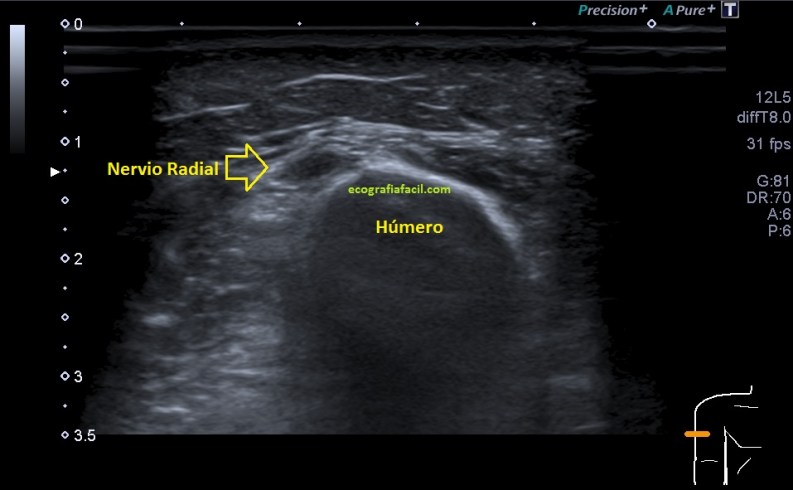

Durante la exploración del hombro me encontré un hallazgo que bien por la experiencia o por la intuición, quizá ambas, busco en cada protocolo de hombro que hago y que es punto de dolor irradiado habitual del hombro justo donde el radial pasa por la parte posterior del húmero antes de buscar la cara antero lateral externa del codo, encontrándome estas imágenes que te comento semiológicamente y que son típicas de neuropatía.

En el lugar comentado anteriormente, encuentro una estructura hipoecogénica que no es compatible con la normalidad de un nervio, como si lo es la imagen 6A que te enseño a continuación donde el nervio radial contralateral te dice cómo es un nervio radial normal en el mismo punto que el de la imagen 6, mira: